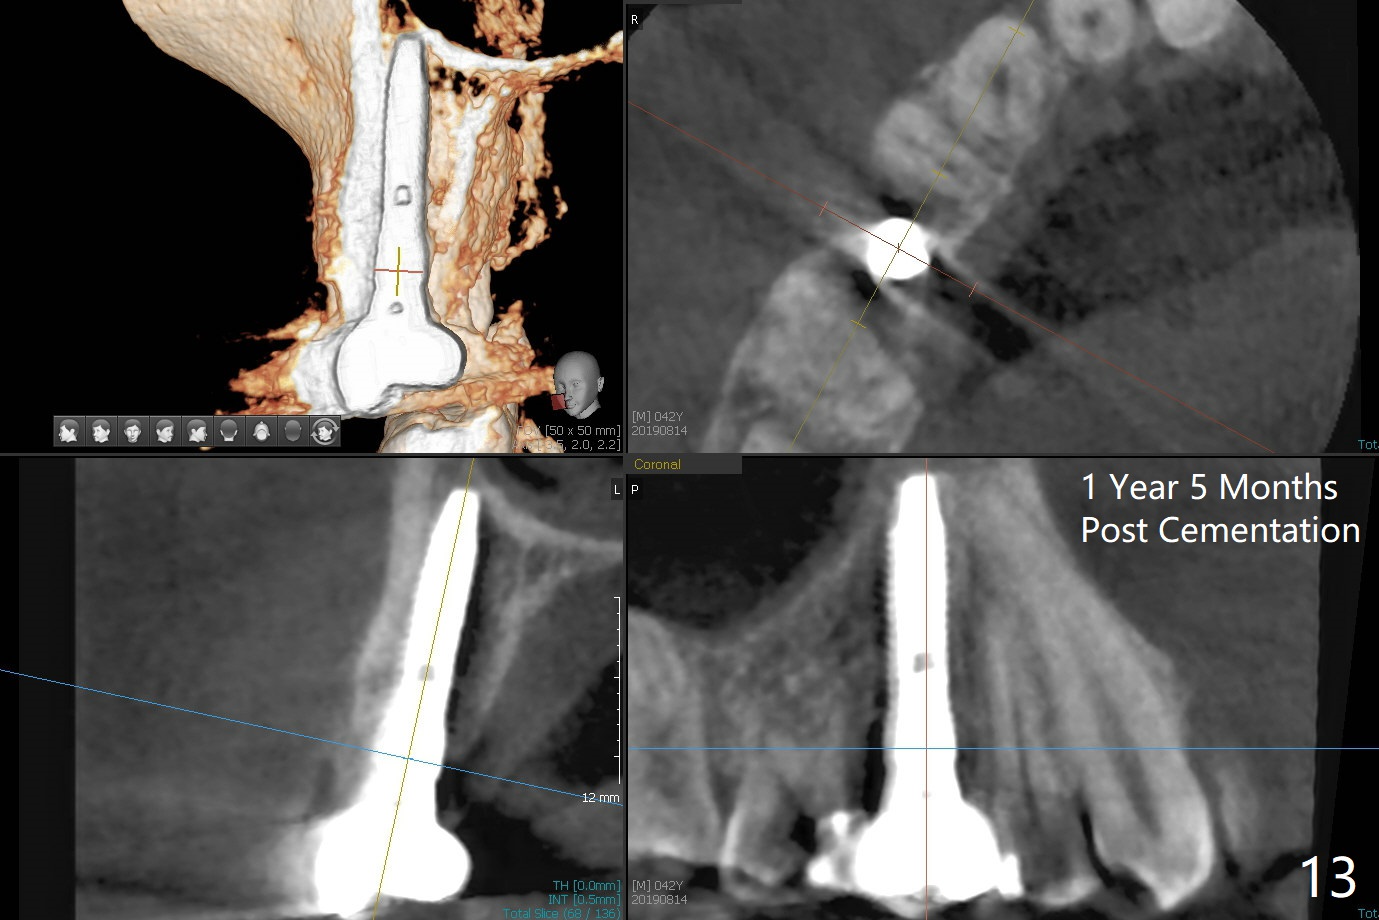

In fact there is a small buccal fistula, which is communicated with the underlying implant threads. Although preop CT shows that the buccal crest is lower than the palatal (3.8x13 mm, Fig.10 P) one, intraop finding of missing buccal plate should dictate a shorter implant (Fig.11) or onlay graft to avoid periimplantitis. Regeneration of the bone plate is limited. Later the fistula disappears with formation of a concavity (Fig.13). There is no symptom. Is bone graft necessary with a remote incision? 3-D images of CT taken 1 year 5 months post cementation show possible mesiobuccal and distopalatal bony defects (Fig.13-16). It is possible that bone graft was placed enough palatal (Fig.16). DO composite at #3 is redo satisfactorily (Fig.17 *).